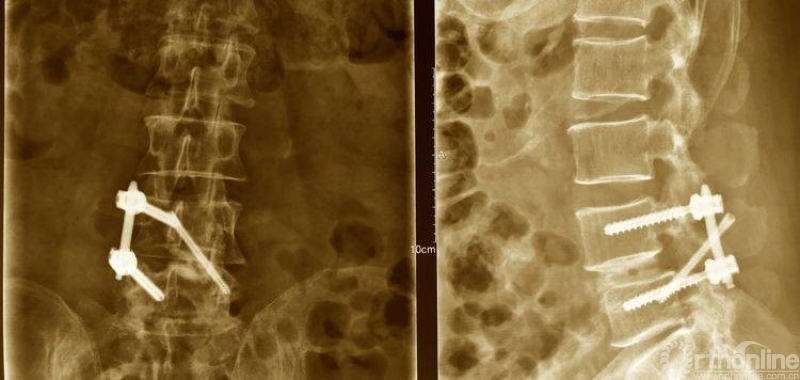

术后资料:

术后正、侧位片

植入钉棒位置较为合理